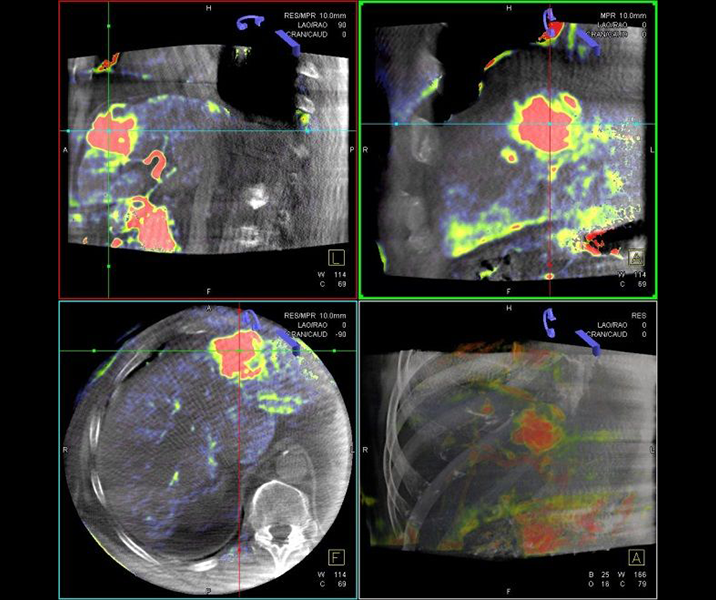

Die Selektive Interne Radiotherapie (SIRT) wird in der Fachliteratur auch Radioembolisation (RE) genannt. Hierbei werden gezielt kleine, radioaktive Kügelchen, sog. Mikrosphären, über den Katheter (siehe TACE) von mehreren Positionen in der Leber mit dem Blutstrom in das gut durchblutete Tumorgewebe gebracht und bleiben dort in den kleinen Gefäßen "stecken", die den Tumor ernähren. Von dort bestrahlt das in den Kügelchen enthaltene radioaktive Element Yttrium-90 über mehrere Tage hinweg das Tumorgewebe und zerstört es selektiv. Dieses Verfahren kann bei Leberkrebs oder -metastasen eingesetzt werden, wenn die Herde trotz Chemotherapie weiter wachsen und nicht chirurgisch oder mittels RFA und TACE behandelbar sind.

Das Verfahren wird von der interventionellen Radiologie zusammen mit der Partnerabteilung der Nuklearmedizin sowie den entsprechenden Partnerkliniken geplant und durchgeführt.

Abbildung Körper: Schematische Darstellung des Zugangsweges bei SIRT-Therapie über die Leistenarterie. Die arteriellen tumorversorgenden Gefäße in der Leber werden selektiv dargestellt und von dort wird die Therapie lokal appliziert. (Bildrechte beim Thieme-Verlag!)